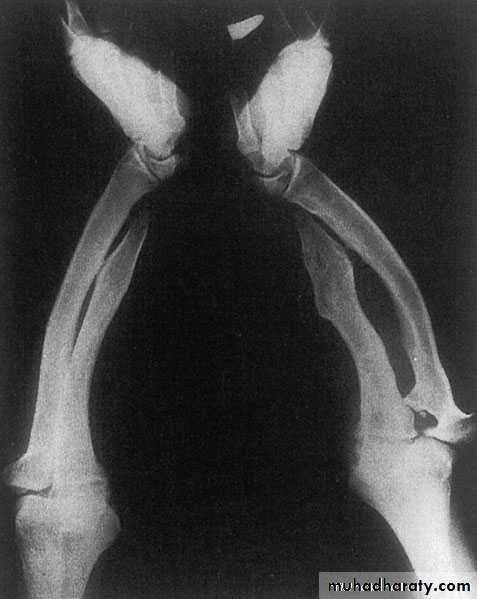

RADIAL DYSPLASIA

rare condition (incidence 1:50 000 to 1:100 000 live births)may involve any (or all) of the structures from the elbow to the thumb, it usually occurs as an isolated abnormality

occasionally associated with other skeletal, cardiac, haematological, renal or craniofacial anomalies

The infant is born with the wrist in marked radial deviation ‘radial club hand’

half the patients are affected bilaterally

There is absence of the whole or part of the radius; often the thumb, scaphoid and trapezium fail to develop normally.